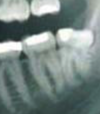

50

assess radiographically

horizontal moderate impaction

51

what other radiographic finding is here of relevance to the 8

overhang of adj 7 restoration - if comes off would need to temporise tooth and work on that later